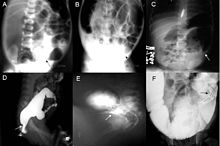

A: Plain abdominal radiograph showing a PARTZ at rectosigmoid, arrow. B: Plain abdominal radiograph showing a PARTZ at midsigmoid, arrow. C: Plain abdominal radiograph showing a PARTZ at descending colon, arrow. D: Contrast enema showing a CETZ at rectosigmoid, arrow. E: Contrast enema showing a CETZ at midsigmoid, arrow. F: Contrast enema showing a CETZ at descending colon, arrow.

Definitive diagnosis is made by suction biopsy of the distally narrowed segment.[26] A histologic examination of the tissue would show a lack of ganglionic nerve cells. Diagnostic techniques involve anorectal manometry,[27] barium enema, and rectal biopsy. The suction rectal biopsy is considered the current international gold standard in the diagnosis of Hirschsprung's disease.[28]

Radiologic findings may also assist with diagnosis.[29] Cineanography (fluoroscopy of contrast medium passing anorectal region) assists in determining the level of the affected intestines.